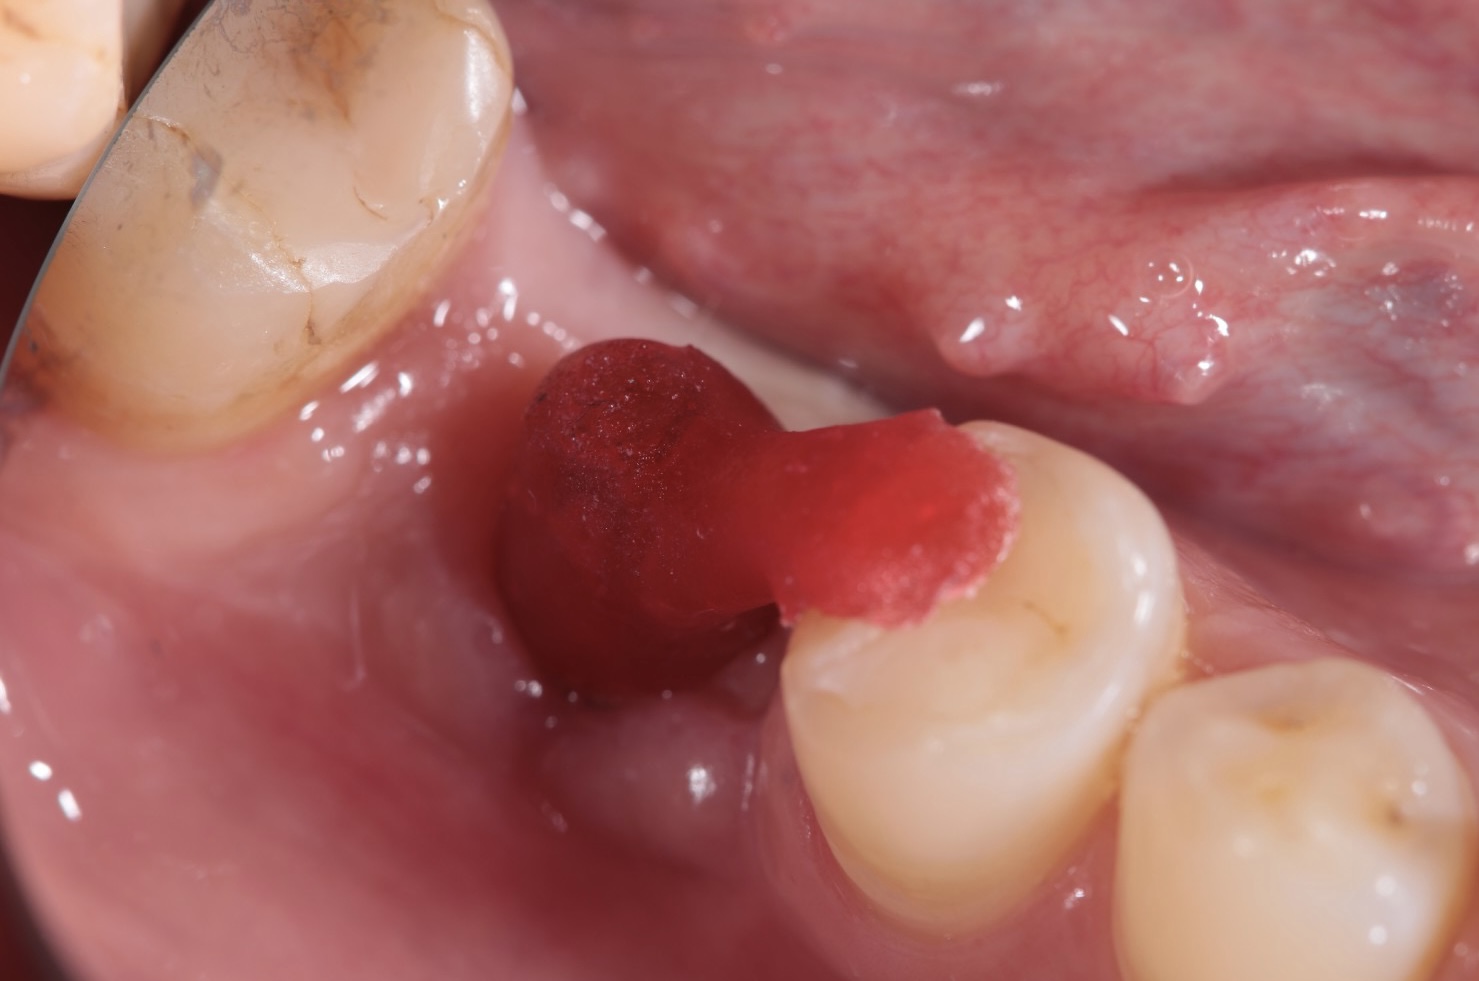

Nekada je ugradnja implanata jednostavna, a nekada je kompleksna i zahteva dodatne hiruške procedure različitog nivoa složenosti da bi se dobili optimalni uslovi za hirurgiju. Naš tim ima znanja, veštine i tehničke mogućnosti za izvođenje svih tih procedura gde se koriste zamenici za kost (“veštačka kost”), kost samog pacijenta, razne vrste membrana (veštačkih ili dobijenih iz krvi samog pacijenta), kao i primena faktora rasta izdvojenih iz krvi sve u cilju dobijanja najboljih uslova za ugradnju implanata i za kasnije protetsko zbrinjavanje kada se pacijent estetski i funkcionalno rehabilituje.